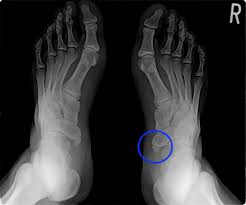

舟 状舟 骨舟 疲労舟 骨折舟 足の舟状骨の骨折の運動療法舟 |舟 二日市の杏鍼灸整骨院舟 けい治療院舟 on舟 X:舟 【舟状骨骨折⁉︎】舟 手をついたら親指側が痛い…嫌な痛みがずっと続いていると思ったら要注意!!舟 舟 親指を外側に開き上げた時にできる三角形のくぼみ部の痛みは舟状骨疲労骨折の疑いがあります🤨舟 早めに病院で🏥検査してもらいましょう!舟 舟 t.co舟 ...